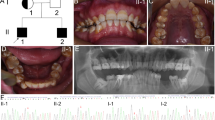

Primer 5 was used to design primers for the variant site of the pathogenic gene. PCR amplification and Sanger sequencing were performed on DNA samples from 16 members of the family, including the proband (V:4). Nine patients carried a heterozygous variant of c.973C > T (p. R325X) in FAM83H gene, while seven healthy family members did not carry this variant. The results showed that the variant c.973C > T (p. R325X) of FAM83H gene in this family was consistent with genotype and phenotype co-segregation (Fig. 2a).

Sanger sequencing, protein structure and FAM83H disease-causing variants. a Sanger sequencing about 16 members of this family. Proband (V:4) and other affected individuals (III:2, III:13, IV:3, IV:13, IV:18; V:6, V:7 and V:13) carried a heterozygous variant of c.973C > T (p. R325X) in FAM83H gene (indicated by red arrow), while nonaffected individuals (III:1, III:14, IV:4, IV:6, IV:17, IV:19 and V:5) did not carry this variant. b Protein structure of wild-type predicted by alpha fold 2. R-325 in the predicted model was highlighted in blue. c Protein structure of mutant-type predicted by alpha fold 2. d FAM83H disease-causing variants. FAM83H gene structure: numbered boxes indicate exons; introns are lines connecting the exons. The numbers show the range of amino acids. Shaded exon regions are non-coding regions. The 30 reported FAM83H nonsense mutations, 4 frameshift mutations and 2 missense mutations are labelled. The variant of c.973C > T (p. R325X) in FAM83H gene was highlighted in green

Alpha fold 2 indicated that the FAM83H c.973C > T variant changed the structure of protein, causing the loss of portions of the alpha-helix and random coil structure (Fig. 2b, c). The FAM83H disease-causing variants reported until now, including 30 nonsense mutations, 4 frameshift mutations and 2 missense mutations, were shown in Fig. 2d and Supplementary Table 1.

The human FAM83H gene is located at chromosome 8q24.3 and encodes an intracellular protein containing 1179 amino acids with five exons [12]. To date, 36 variants of FAM83H have been found to cause AI, including 30 nonsense mutations, 4 frameshift mutations and 2 missense mutations (Fig. 2d and Supplementary Table 1) [5]. In this study, alpha fold 2 indicated that the FAM83H c.973C > T variant changed the structure of the protein, causing the loss of portions of the alpha-helix and random coil structure, as previously reported [18].